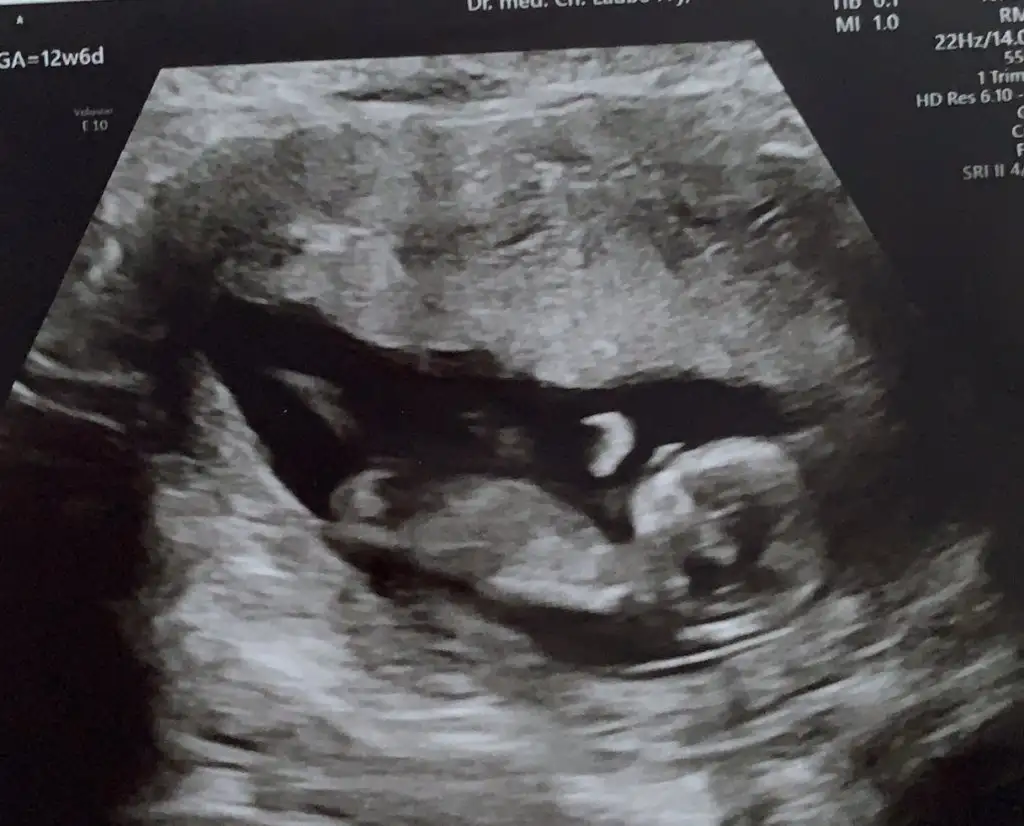

USG net değil ama nubu dik görünüyorSimdi 17 haftaligiz. Bu resimlerdede 12 haftaydi

Çok büyük gelmedi bana emin olamadım popoyada paralel değil acısı hafif dik geldi başka USG varsa teyit etmek isterimAttım tekrar bundan baslada yok 12+3

Başka yok sadece bu var tahmini hangiisnden yana kullanmak istersinÇok büyük gelmedi bana emin olamadım popoyada paralel değil acısı hafif dik geldi başka USG varsa teyit etmek isterimEki Görüntüle 2751139